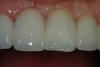

Figure 8  Completed direct composite restorations on tooth Nos. 8 and 9.

Figure 8